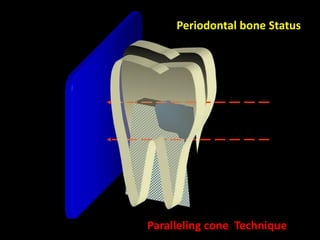

2. The paralleling cone technique provides accurate images with little magnification and no superimposition but is more difficult for patients. The bisecting angle technique is easier for patients but results in more image distortion.